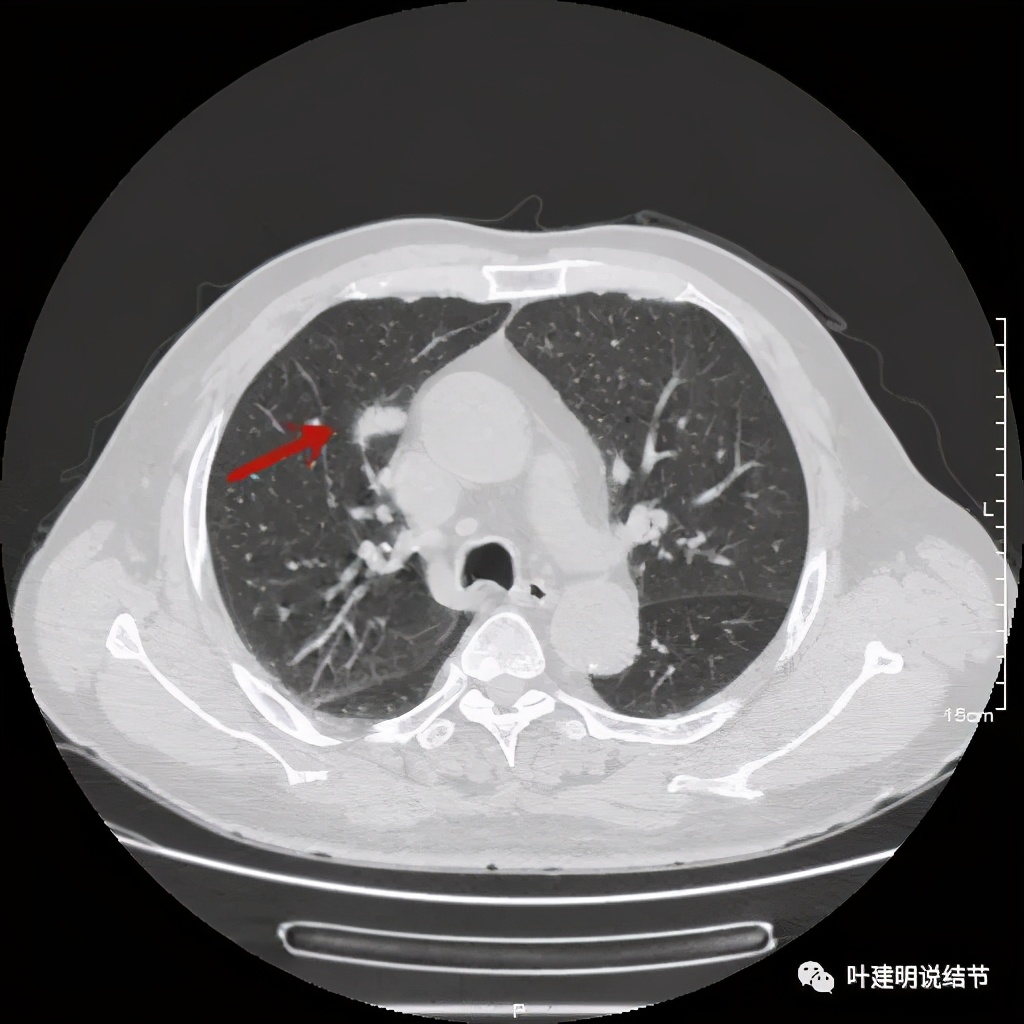

上图示病灶密度不均

上图示病灶局部点状高密度(蓝色);边缘过于光滑(绿色)

上图示病灶密度不均,但边缘过于光滑(绿色);支气管似有截断(粉色);局部有点状钙化(蓝色)